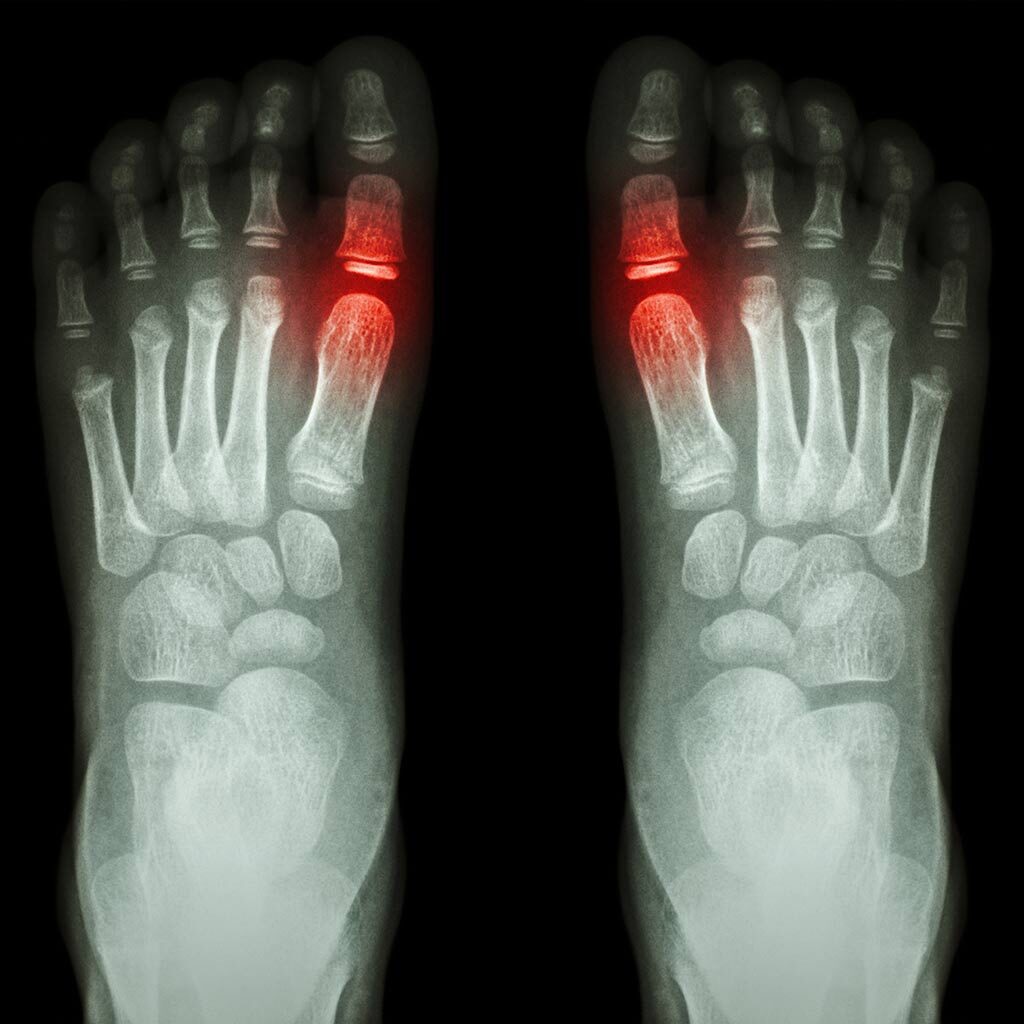

Digital radiology has revolutionized podiatric care over the past decade. Digital x-rays in Bethesda, MD, and Springfield, VA, allow our podiatrists to take and magnify an image of your foot with crystal clear details that enable them to tell stress fractures apart from other abnormalities. It ensures a proper diagnosis of painful foot and ankle conditions with the ability to view this immediately in the office.

We also use digital x-rays to monitor your foot’s structure on an ongoing basis in order to evaluate and treat any chronic foot conditions. In some cases, our podiatrists may use digital x-rays to guide them during surgical procedures and to share results with other doctors, as you wish.